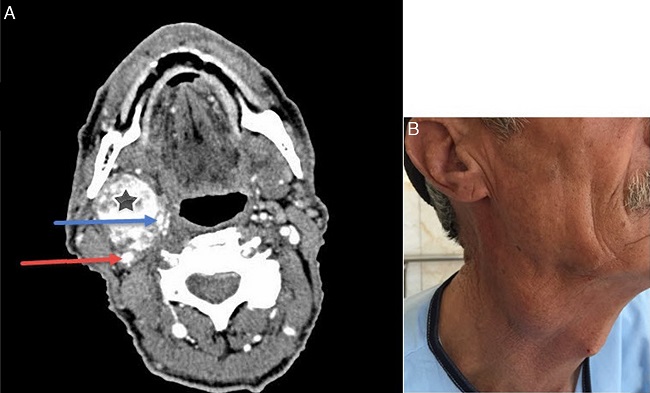

A 60 year-old man referred to the otolaryngology clinic of the Firoozgar hospital complaining of a painless, pulsatile right neck mass with a gradual growth since 40 years ago (Fig. 1).

In the cervical CT scan, a heterogeneous 39 mm × 40 mm × 62 mm solid mass was detected in the right carotid artery bifurcation, from the oropharynx level to the supraglot, splitting the carotid artery branches with a significant enhancement.

Transcranial Color-Coded duplex Sonography (TCCS) reported normal anterior and posterior Peak Systolic Velocities (PSVs) and Mean Flow Velocities (MFVs). Normal flow velocity and direction in right and left ECAs (External Carotid Arteries), ICAs and CCAs with increased right and left CCAs Intima-Media Thickness (IMT). A vascularized mass-like lesion was also reported inside the carotid artery bifurcation (suggesting carotid body tumor) in addition to grade B (0-15%) stenosis in left and right ICAs.